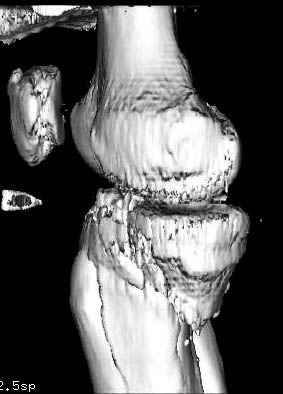

Здесь как раз тот случай, когда результат зависит не только от мастерства хирурга, но и от наличия современных методов исследования. Например, КТ которая поможет рассчитать направления шурупов и установку импланта. Кроме этого, поможет определиться с доступом.

На представленных предоперационных срезах КТ огромный задне-медиальный фрагмент расположен больше кзади, чем медиально. Для планирования, кроме поперечных срезов, надо ориентироваться на корональные срезы, которые укажут топографию верхушки медиального фрагмента.

Надеюсь, представленные снимки разных случаев помогут разобраться в тактике, и критика примется без личной обиды.